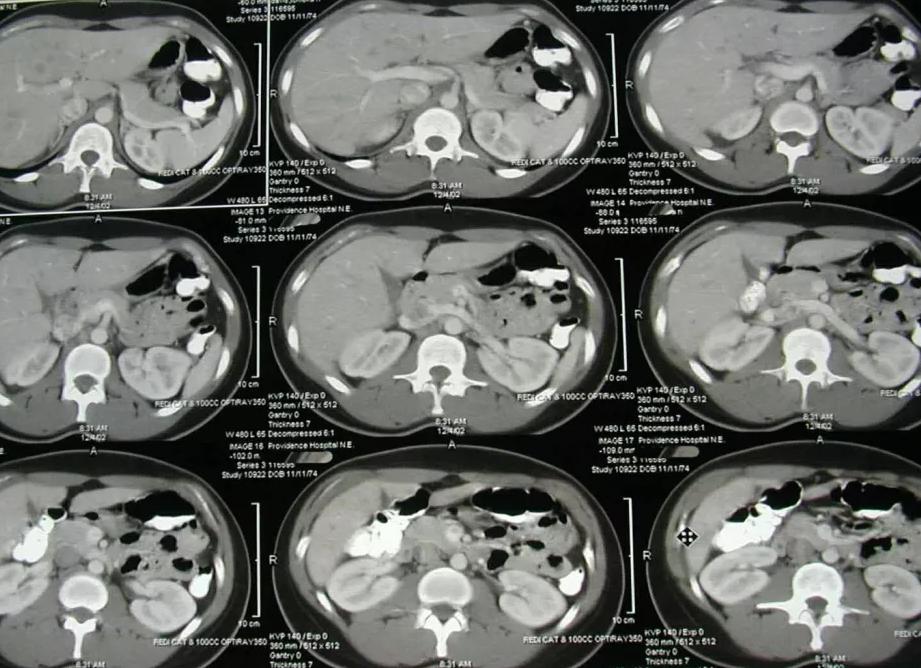

В ходе процедуры КТ внутренние органы человека сканируются в трех разных плоскостях, а полученная информация фиксируется в виде трехмерных снимков.

Применимо к брюшной полости процедура КТ позволяет оценить не только визуальное состояние расположенных в ней органов, но и плотность составляющих тканей.

Фото:

Поэтому с помощью компьютерной томографии нередко удается установить те внутренние изменения, которые не были доступны в ходе других диагностических процедур.

Во время проведения томографии проводится трехмерная визуализация органа брюшной полости, получается его «срез», что помогает рассмотреть не только форму, но и структуру.

Компьютерная томография — современный метод диагностики, благодаря которому можно увидеть четкую картину всех органов, расположенных в брюшной полости и за ее пределами. Главным преимуществом КТ является возможность получения трехмерной картинки, благодаря чему все органы и близлежащее ткани видны в послойном размере из трех плоскостей.